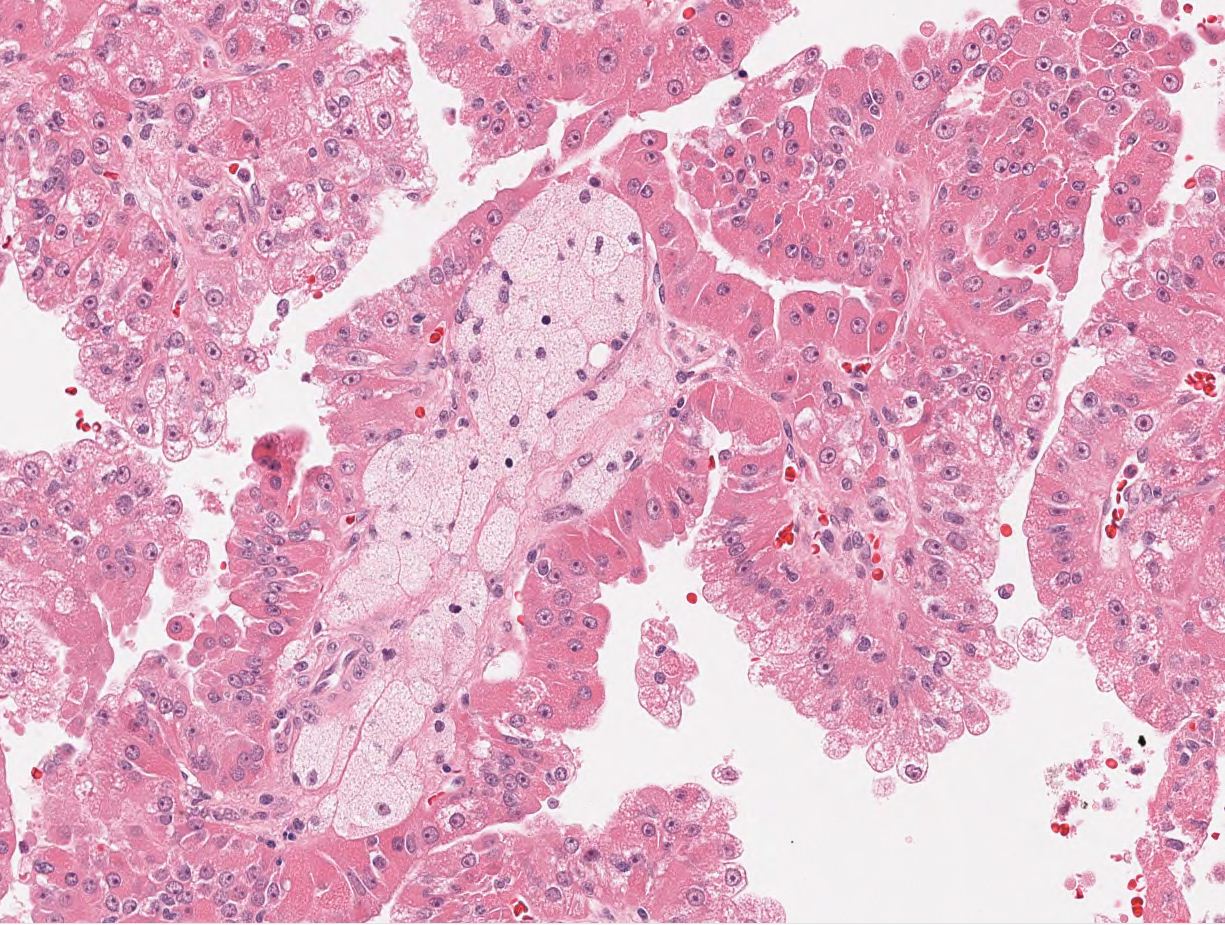

Renal tumor grading

Case ID: 564